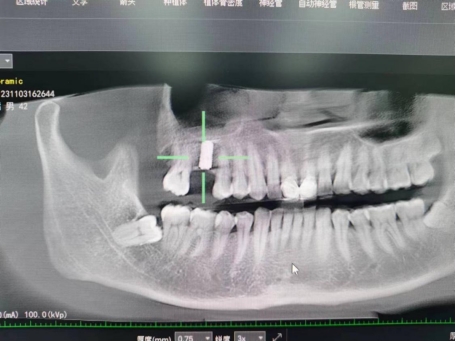

武先生术后检查图

据了解,53岁的武先生,因右上后牙缺失多年,缺失的牙齿给他造成了不小的烦恼,影响到了正常咀嚼功能。在了解到公司口腔科能开展种植牙手术以后,武先生前来咨询,经过仔细全面的口腔检查和CT检查、检验等检查,武先生符合种植牙条件,决定实施右上后牙区种植牙的修复方案。本次手术由陈河林博士主刀,黄魁副主任做助手,在口腔中心成功完成该院首例种植牙手术,手术历时约30分钟,术中微创操作,患者全程无痛,术后无不良反应,整个诊疗过程舒适、安全、精准,经术后CT检查种植体位置精确。